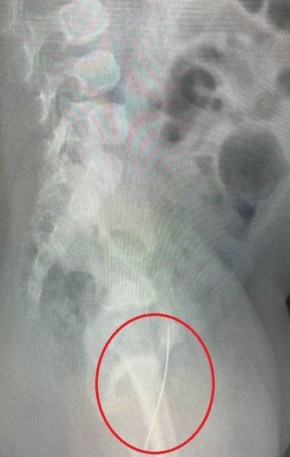

В Информационный центр СК России поступило обращение жительницы Московской области по вопросу несогласия с ходом установления обстоятельств травмирования ее четырехлетней дочери-инвалида в городе Жуковском. В сентябре текущего года после возвращения девочки из детского сада заявительница обнаружила у нее телесные повреждения. Обращения в компетентные органы результатов не принесли, до настоящего времени никто к ответственности не привлечен.